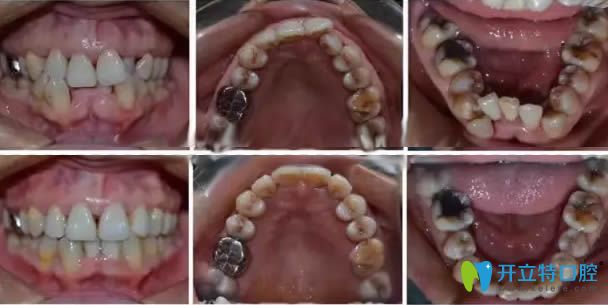

顧客:王姐,43歲,整牙一直是她的心愿,早年因為做生意忙還要照顧孩子,所以一直拖著,現(xiàn)在孩子大了,是時候給牙齒做個美好的改變了;

口腔癥狀:牙列不齊擁擠、齲齒、牙齦炎癥;

主治醫(yī)師:杜如;

治療方案:齲齒治療后,拔牙+時代天使隱形牙套矯正;

治療效果:王姐嚴格按照醫(yī)囑認真佩戴隱形矯正器,多次定期復(fù)診,一年半后終于成功結(jié)束了矯正。43歲的王姐,在牙齒矯正行列中屬于是年紀偏大的,但并不影響后期矯治的效果。從圖片可以看出來,矯正的效果非常成功,張姐本人也表示非常滿意。